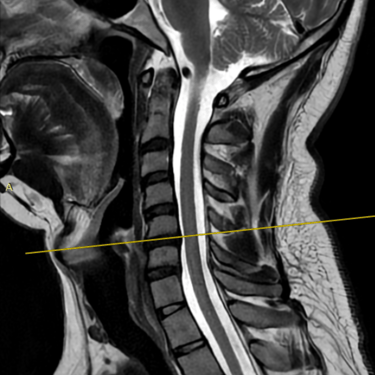

Discopatía Cervical con Inestabilidad de Columna | Diagnóstico por Resonancia Magnética

La discopatía cervical con inestabilidad de columna es una patología que compromete la movilidad y estabilidad de la región cervical, generando síntomas como dolor cervical crónico, rigidez, irradiación a miembros superiores y, en casos avanzados, déficit neurológico. La resonancia magnética (RMN) es el método diagnóstico de elección, ya que permite evaluar la degeneración discal, protrusiones o hernias discales, cambios en los cuerpos vertebrales, compresión radicular y signos de inestabilidad. Su precisión ayuda a planificar el tratamiento más adecuado, que puede incluir manejo conservador o cirugía, según la gravedad y el compromiso neurológico del paciente.